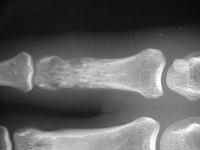

Painful prominence on index finger proximal phalanx in a gentleman with known metastatic squamous cell lung cancer.

Radiographic erosive changes of the proximal phalanx.